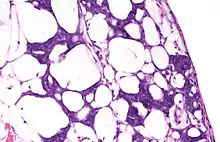

During the last century, blastemas were thought to be composed of undifferentiated pluripotent cells, but recent research indicates that in some organisms blastemas may retain memory of tissue origin.[3] They are typically found in the early stages of an organism's development such as in embryos, and in the regeneration of tissues, organs and bone.[4]

When the limb of the salamander is cut off, a layer of epidermis covers the surface of the amputation site. In the first few days after the injury, this wounded epidermis transforms into a layer of signaling cells called the Apical Epithelial Cap (AEC), which has a vital role in regeneration. In the meantime, fibroblasts from the connective tissue migrate across the amputation surface to meet at the center of the wound. These fibroblasts multiply to form a blastema, the progenitor for a new limb.[7]

As stated above, there are several different types of organisms that can utilize a regenerative blastema as an adult. These organisms include urodele amphibians, zebrafish, and planarian flatworms as major creatures of study. In flatworms, the formation of a blastema needs adult stem cells that are called neoblasts for any type of regeneration to occur.[11] Flatworms use these undifferentiated cells for regeneration after paracrine factors can provide signals from the surface of the wound. The cells in the blastema are also referred to as clonogenic neoblasts (cNeoblasts) that are able to move to the site of the wound and reform the tissue.[12] In urodele amphibians, studies suggest that dedifferentiation of cells leads to the formation of a blastema that is able to form multiple tissue types after the amputation of their tails and wound healing occurs.[13][14] In zebrafish, and in general, it seems as if experts are still uncertain of what truly forms the blastema. However, two common theories that have often been expressed are cell dedifferentiation and the recruitment of stem cells to the wound site.[15]